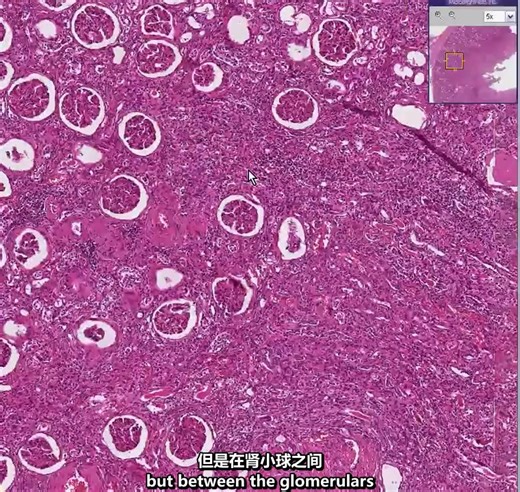

| 肾病理切片 | 急性和慢性肾盂肾炎 | Histopathology Kidney-- Acute an

Chronic Pyelonephritis - Kidney, Histopathology